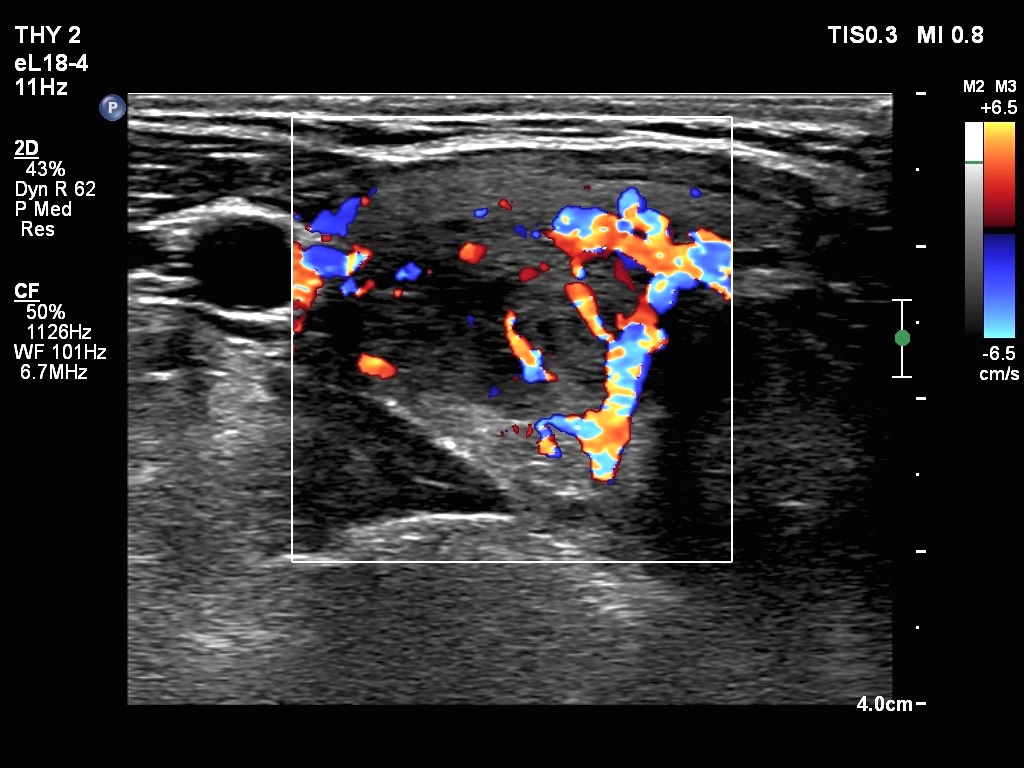

Ultrasonography. The thyroid was echonormal. There were two nodules in the right lobe. The upper was hyperechogenic-cystic while the lower was a minimally-moderately hypoechogenic. The latter had irregular, lobulated margins. There was a hypoechoic area in the upper two-third of left lobe. The discrete area presented ill-defined margins and decreased vascularization. A spongiform cyst was found in the lower pole of the left lobe.

Cytology of the nodule with irregular margins resulted in benign lesion, while cytology disclosed de Quervain's thyroiditis in the event of the hypoechoic area in the left lobe.